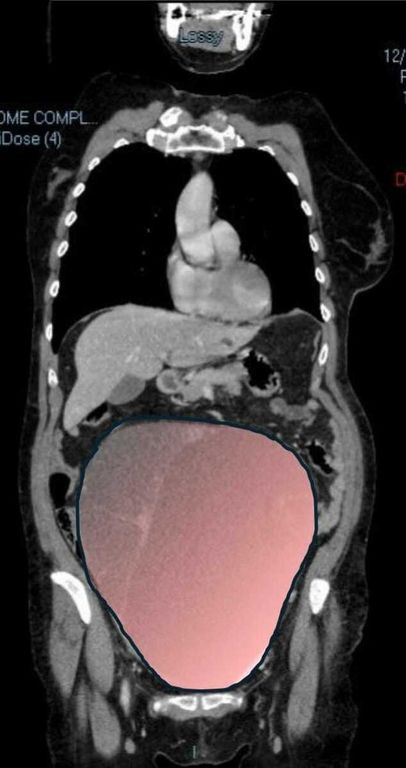

Non avvertiva dolore e non immaginava ciò che stava crescendo silenziosamente dentro di lei. Una donna di 69 anni ha scoperto di essere affetta da un tumore ovarico di dimensioni eccezionali, paragonabile a una gravidanza gemellare a termine, solo quando il suo organismo ha improvvisamente iniziato a cedere a metà dicembre.

Il caso, definito dai medici un evento “normalmente eccezionale”, è stato preso in carico dalla Chirurgia Ginecologica mininvasiva dell’ospedale Sant’Anna di Torino, diretta dal dottor Paolo Petruzzelli. Nonostante le festività imminenti, la macchina della sanità piemontese si è attivata con una rapidità straordinaria: il 23 dicembre la paziente è stata sottoposta a un intervento durato sei ore che ha visto l’asportazione di una massa di ben 6 chilogrammi e un diametro di 28 centimetri.